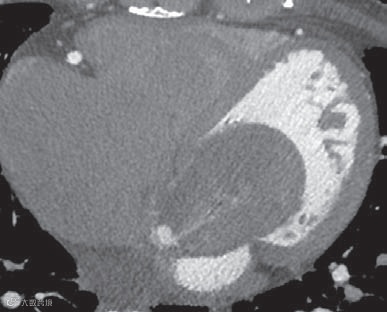

显示肿物边界清晰,有包膜,内部结构均匀,但未发现实性病变(图10和11)。以上检查均未显示肿瘤侵犯的证据,如房间隔不均匀或增厚,以及肿瘤向其他心腔延伸。

术前怀疑为伴有瘤内出血的左心房黏液瘤。心脏内囊性肿物的鉴别诊断包括支气管囊肿、包虫囊肿、血栓、房室结囊性肿瘤、心脏内静脉曲张、闭合性房间隔动脉瘤和心内膜血囊肿。